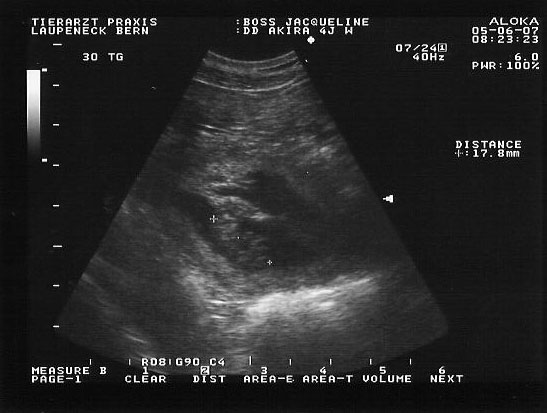

sind wir zum Tierarzt gefahren zum Röntgen, um zu schauen ob nun alle

Welpen Geboren sind. Erstaunt haben wir festgestellt das noch 4

Nachzügler drin sind.

Also bekam Akira Wehenmittel gespritzt, leider ohne Erfolg, die Wehen

blieben aus.

Also war schweren Herzens ein Kaiserschnitt nötig.